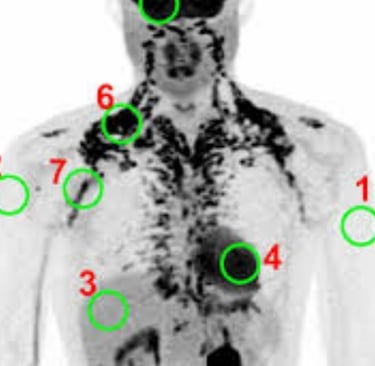

The ¹⁸F-FDG PET-CT scan has been a common method for assessing BAT.

When BAT is active, it uses up glucose, which is marked by the radioactive FDG tracer to show where the BAT is.

1. Xenon-Enhanced CT (Xe-CT): A More Accurate Option

Xenon-Enhanced CT is a big jump forward.

Recent studies that compared it directly with PET/CT suggest that Xe-CT could be more accurate for measuring BAT.

Since BAT has many blood vessels, it absorbs inhaled xenon gas rapidly.

This provides a strong signal that measures how well the tissue is functioning.